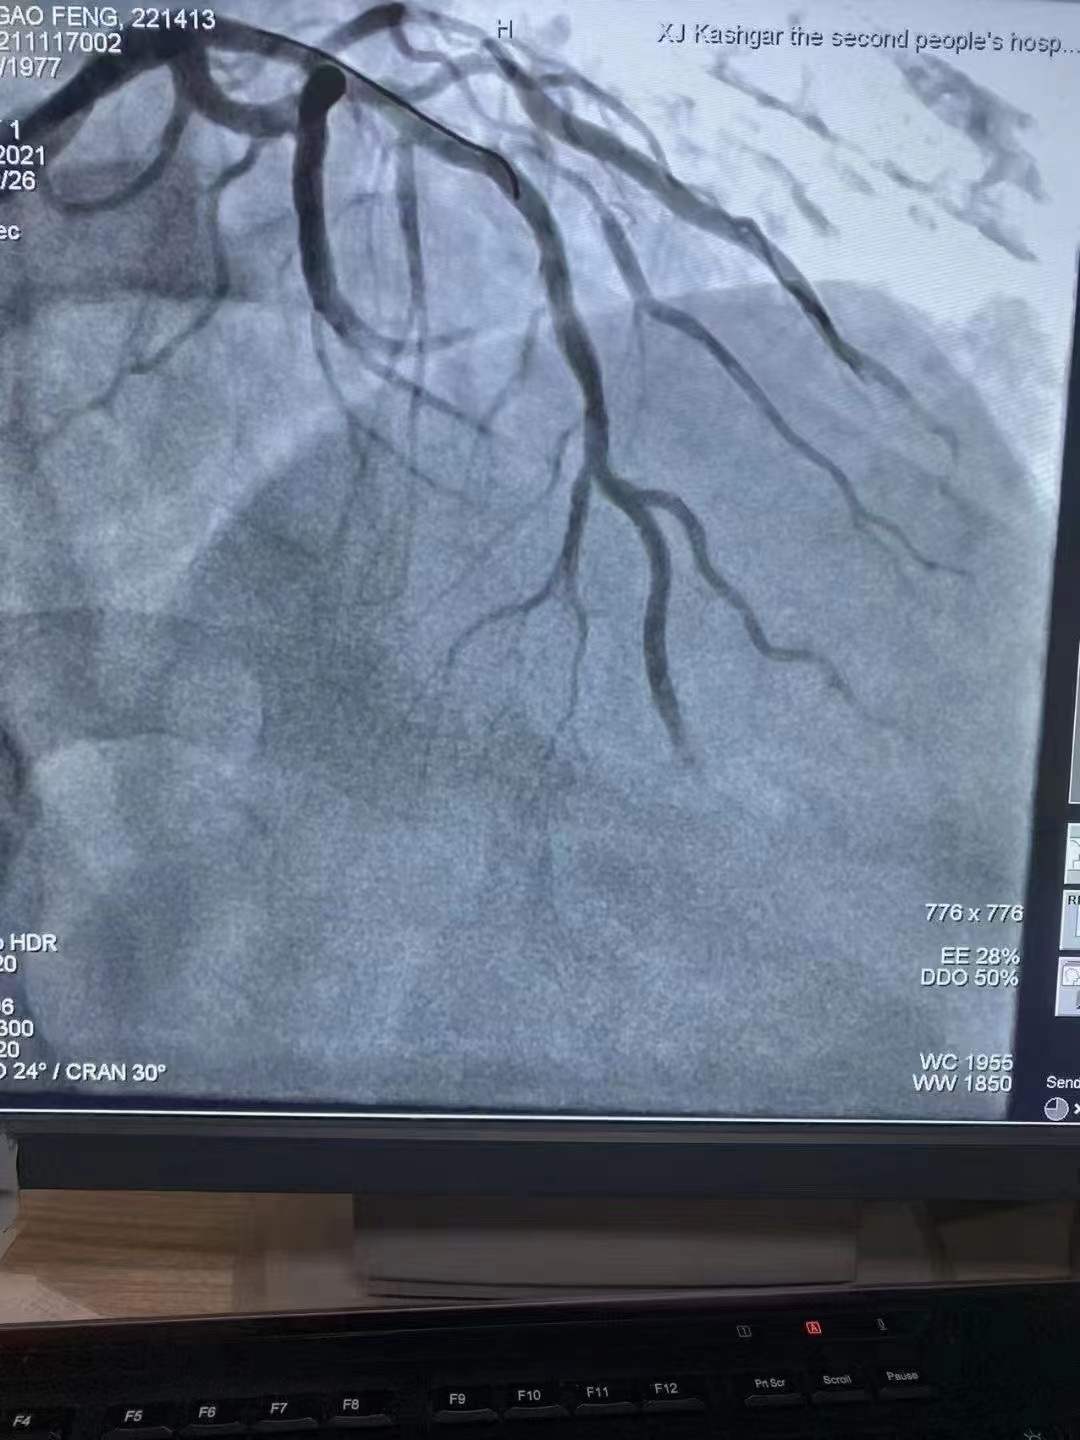

祝賀 新疆喀什地區(qū)第二人民醫(yī)院心內(nèi)科在復(fù)旦大學(xué)中山醫(yī)院援疆專家姚志峰主任帶領(lǐng)下成功為患者植入新疆首例Xinsorb生物可吸收支架,感謝援疆項(xiàng)目的扎實(shí)落地,溫暖了新疆各族百姓Xinsorb與白衣天使共同守護(hù)每一個心臟!